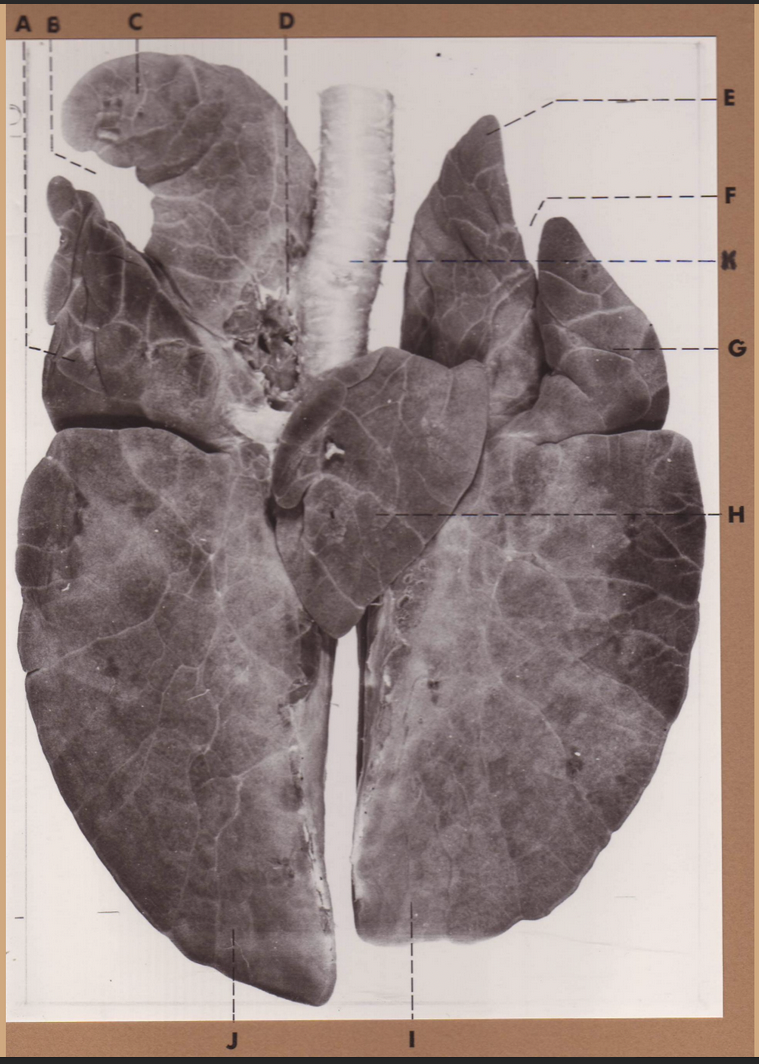

A

(dog lungs, dorsal)

L cranial lobe

B

(dog lungs, dorsal)

cranial segment, L cranial lobe

C

(dog lungs, dorsal)

caudal segment, L cranial lobe

D

(dog lungs, dorsal)

apex

E

(dog lungs, dorsal)

trachea

F

(dog lungs, dorsal)

R cranial lobe

G

(dog lungs, dorsal)

middle lobe

H

(dog lungs, dorsal)

R caudal lobe

I

(dog lungs, dorsal)

accessory lobe

J

(dog lungs, dorsal)

L caudal lobe